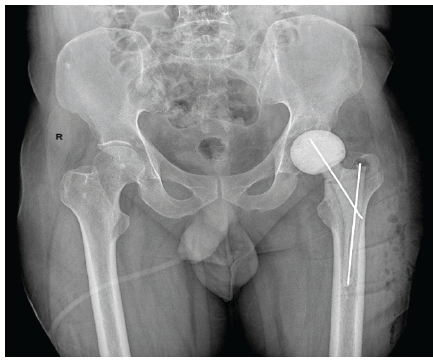

A 52-year-old male with CKD on maintenance hemodialysis for 5 years presented with gradually worsening left hip pain and reduced mobility over 18 months. Clinical examination revealed painful restriction of motion. Radiograph (Fig. 1) and magnetic resonance imaging showed advanced destructive arthritis of the hip. A two-stage surgical procedure was planned. In stage one (Fig.2), thorough debridement was performed, and an antibiotic-impregnated cement spacer was placed (Fig.3). Intra-operative tissue cultures grew Candida guilliermondii. The patient was treated with intravenous Caspofungin for six weeks, after which inflammatory markers normalised.

Figure 3: Post-operative radiograph following stage-1 surgery demonstrating antibiotic cement spacer.